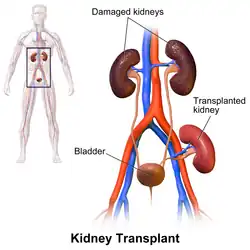

Kidney transplant or renal transplant is the organ transplant of a kidney into a patient with end-stage kidney disease (ESRD). Kidney transplant is typically classified as deceased-donor (formerly known as cadaveric) or living-donor transplantation depending on the source of the donor organ. Living-donor kidney transplants are further characterized as genetically related (living-related) or non-related (living-unrelated) transplants, depending on whether a biological relationship exists between the donor and recipient. The first successful kidney transplant was performed in 1954 by a team including Joseph Murray, the recipient's surgeon, and Hartwell Harrison, surgeon for the donor. Murray was awarded a Nobel Prize in Physiology or Medicine in 1990 for this and other work.[1] In 2018, an estimated 95,479 kidney transplants were performed worldwide, 36% of which came from living donors.[2]

Before receiving a kidney transplant, a person with ESRD must undergo a thorough medical evaluation to make sure that they are healthy enough to undergo transplant surgery. If they are deemed a good candidate, they can be placed on a waiting list to receive a kidney from a deceased donor.[3] Once they are placed on the waiting list, they can receive a new kidney very quickly, or they may have to wait many years; in the United States, the average waiting time is three to five years.[4] During transplant surgery, the new kidney is usually placed in the lower abdomen (belly); the person's two native kidneys are not usually taken out unless there is a medical reason to do so.[3]

Procedure

In most cases, the barely functioning existing kidneys are not removed, as removal has been shown to increase the rates of surgical morbidity. Therefore, the kidney is usually placed in a location different from the original kidney. Often, this is in the iliac fossa, so it is often necessary to use a different blood supply:

- The renal artery of the new kidney, previously branching from the abdominal aorta in the donor, is often connected to the external iliac artery in the recipient.

- The renal vein of the new kidney, previously draining to the inferior vena cava in the donor, is often connected to the external iliac vein in the recipient.

The donor ureter is anastomosed with the recipient bladder. In some cases, a ureteral stent is placed at the time of the anastomosis, with the assumption that it allows for better drainage and healing. However, using a modified Lich-Gregoir technique, Gaetano Ciancio developed a technique that no longer requires ureteral stenting, avoiding many stent-related complications.[63]

Post operation

The transplant surgery takes about three hours.[65] The donor kidney will be placed in the lower abdomen and its blood vessels connected to arteries and veins in the recipient's body. When this is complete, blood will be allowed to flow through the kidney again. The final step is connecting the ureter from the donor kidney to the bladder. In most cases, the kidneys will soon start producing urine.